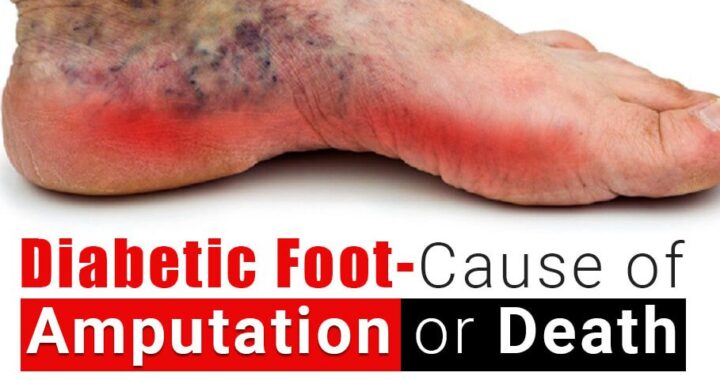

Ancaman Amputasi pada Penderita Kencing Manis akibat Diabetic Foot

Diabetes Melitus (DM) merupakan penyakit metabolik kronis yang ditandai dengan tingginya kadar gula darah akibat gangguan produksi atau kerja insulin dalam tubuh. Salah satu komplikasi serius dari DM adalah Diabetic Foot (DF) atau kaki diabetik, yaitu kondisi kerusakan jaringan pada kaki yang disebabkan oleh kombinasi neuropati (kerusakan saraf), gangguan aliran darah (iskemia), dan infeksi. Kaki diabetik menjadi masalah kesehatan yang signifikan karena dapat berkembang menjadi luka kronis yang sulit sembuh, bahkan berujung pada amputasi jika tidak ditangani dengan baik. Kondisi ini sering kali diawali dengan hal-hal sederhana seperti luka kecil, lecet, atau tekanan berlebih pada kaki yang tidak dirasakan oleh penderita akibat menurunnya sensitivitas saraf. Oleh karena itu, pemahaman tentang DM dan komplikasinya, khususnya DF, sangat penting untuk mencegah dampak yang lebih serius.

Penyebab utama terjadinya diabetic foot adalah neuropati diabetik dan penyakit pembuluh darah perifer yang sering dialami oleh penderita diabetes dalam jangka panjang. Neuropati menyebabkan hilangnya sensasi nyeri, panas, atau dingin pada kaki, sehingga penderita tidak menyadari adanya luka atau cedera. Sementara itu, gangguan sirkulasi darah menghambat proses penyembuhan luka karena jaringan tidak mendapatkan cukup oksigen dan nutrisi. Selain itu, kadar gula darah yang tinggi juga menciptakan lingkungan yang ideal bagi pertumbuhan bakteri, sehingga meningkatkan risiko infeksi. Faktor risiko lainnya meliputi kontrol gula darah yang buruk, kebiasaan merokok, penggunaan alas kaki yang tidak sesuai, serta kurangnya perawatan kaki. Kombinasi dari faktor-faktor ini menjadikan kaki sebagai bagian tubuh yang sangat rentan pada penderita diabetes.

Gejala diabetic foot dapat bervariasi tergantung pada tingkat keparahan kondisi. Pada tahap awal, mungkin hanya terlihat perubahan warna kulit, kulit kering, atau kapalan. Seiring perkembangan kondisi, dapat muncul luka terbuka (ulkus), pembengkakan, bau tidak sedap, hingga keluarnya cairan atau nanah dari luka. Pada kasus yang lebih berat, jaringan kaki dapat mengalami kematian (gangren), yang sering kali ditandai dengan perubahan warna menjadi hitam. Diagnosis biasanya dilakukan melalui pemeriksaan fisik, evaluasi saraf, serta pemeriksaan aliran darah pada kaki. Penanganan diabetic foot memerlukan pendekatan multidisiplin, termasuk kontrol gula darah yang ketat, perawatan luka yang tepat, penggunaan antibiotik jika terdapat infeksi, serta tindakan bedah jika diperlukan. Perawatan luka modern juga sering melibatkan teknik seperti debridement (pembersihan jaringan mati) dan penggunaan balutan khusus untuk mempercepat penyembuhan.

Pencegahan diabetic foot merupakan langkah yang paling efektif untuk mengurangi risiko komplikasi serius. Penderita diabetes dianjurkan untuk melakukan pemeriksaan kaki secara rutin setiap hari, menjaga kebersihan dan kelembapan kulit, serta menggunakan alas kaki yang nyaman dan sesuai ukuran. Memotong kuku dengan hati-hati dan menghindari berjalan tanpa alas kaki juga sangat penting untuk mencegah cedera. Selain itu, kontrol gula darah yang baik melalui pola makan sehat, olahraga teratur, dan kepatuhan terhadap pengobatan merupakan kunci utama dalam mencegah berbagai komplikasi diabetes, termasuk kaki diabetik. Edukasi kepada pasien dan keluarga juga memainkan peran penting dalam meningkatkan kesadaran dan kepatuhan terhadap perawatan. Dengan pencegahan yang tepat dan penanganan dini, risiko amputasi akibat diabetic foot dapat ditekan secara signifikan, sehingga kualitas hidup penderita diabetes tetap terjaga.